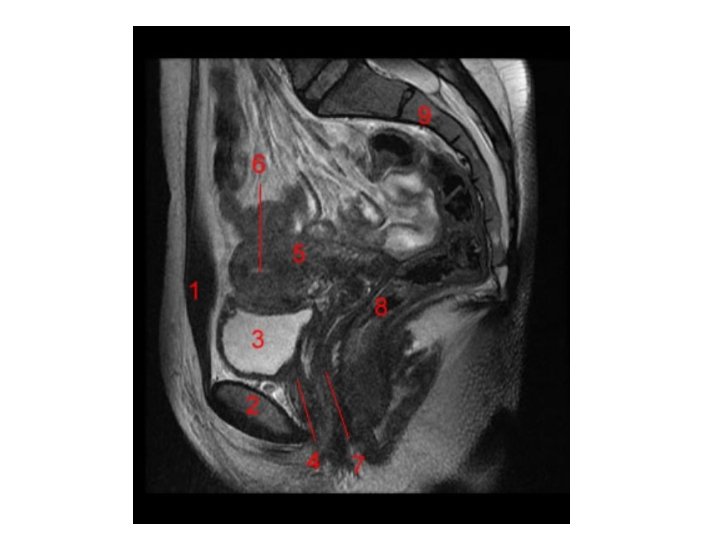

Vagina Excavatio vesicouterina Peritoneum Excavatio rectouterina Uterus Portio vaginalis cervicis Vesica urinaria Portio supravaginalis cervicis Fornix vaginae, Pars posterior Fornix vaginae, Pars anterior Vagina, Paries anterior Rectum Urethra Septum rectovaginale Septum vesicovaginale Vagina, Paries posterior Ostium vaginae Vestibulum vaginae Diaphragma urogenitale